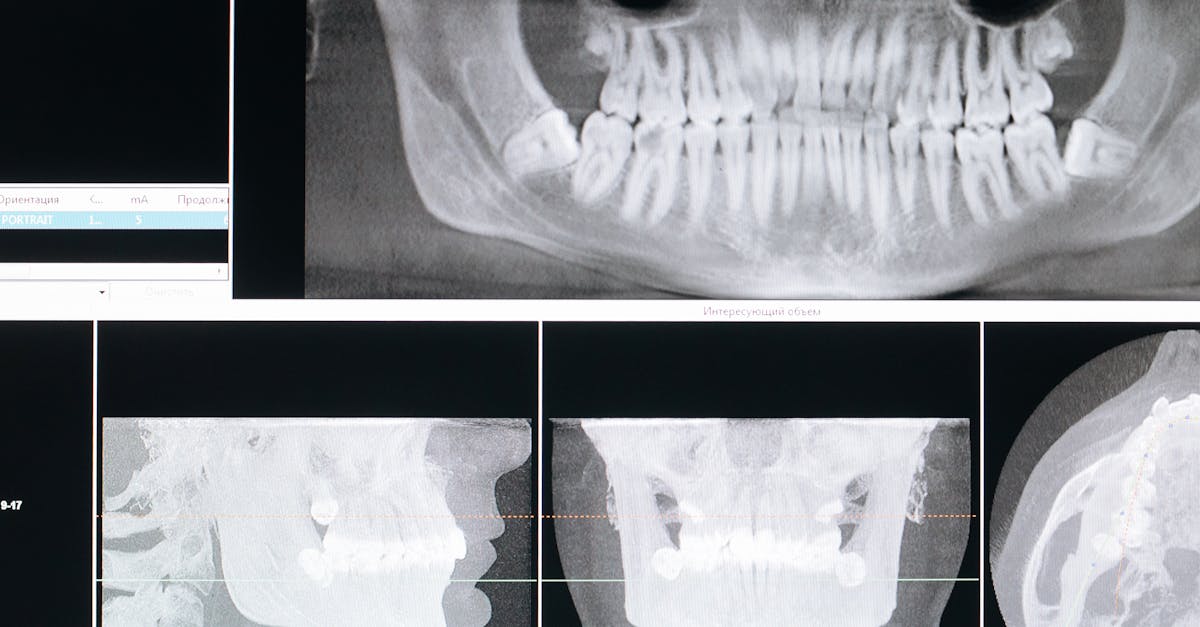

Après l’examen physique, des examens complémentaires peuvent être nécessaires. Des imageries médicales comme des IRM ou des radiographies permettent de visualiser l’état des disques intervertébraux et de détecter des anomalies telles que des hernies discales ou des pincements nerveux. Ces résultats fournissent des informations précieuses qui influenceront directement le traitement proposé.

- Tests diagnostiques : Réaliser des examens complémentaires, tels que l’IRM ou des radiographies, pour visualiser les structures vertébrales.

Selon les résultats de l’examen physique, des tests supplémentaires peuvent être envisagés, tels que des radiographies, des IRM ou des scanners. Ces examens d’imagerie fournissent des informations détaillées sur la structure de la colonne vertébrale et peuvent aider à diagnostiquer des conditions spécifiques, comme les hernies discales ou les sténoses.

| 3. Examens d’imagerie | Utilisation de techniques comme l’IRM ou la radiographie pour visualiser les disques intervertébraux. |

En parallèle du diagnostic physique, des examens complémentaires peuvent s’avérer nécessaires. Parmi ceux-ci, des imageries médicales comme l’IRM ou la radiographie sont souvent prescrites pour visualiser l’état précis des disques intervertébraux ainsi que des structures vertébrales. Ces examens aident à détecter des anomalies telles que des hernies discales ou d’autres pathologies qui pourraient nécessiter une attention particulière lors du traitement par décompression neurovertébrale. L’importance de cette étape réside dans la capacité à confirmer ou infirmer les hypothèses initiales posées par le praticien lors de l’évaluation des symptômes du patient.

La première étape consiste en une évaluation médicale approfondie, où le professionnel de santé examine les antécédents médicaux du patient et réalise des tests physiques. Cela inclut des évaluations de la posture, de la mobilité, ainsi que l’utilisation d’examens d’imagerie comme des IRM ou des radiographies. Ces outils permettent de visualiser l’état des disques intervertébraux et de déterminer exactement l’origine des douleurs.